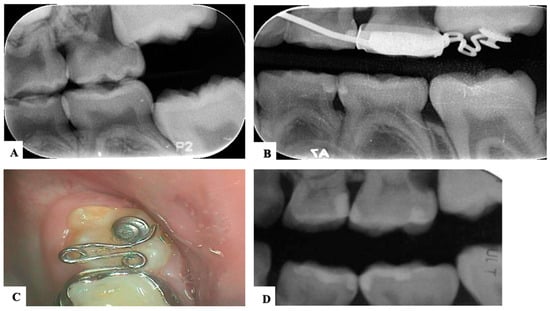

| Barberia-Leache ’s Classification (Based on the effect on second primary molar) * | |||||

| Grade 1 Mild | Grade 2 Moderate | Grade 3 Severe | Grade 4 Very severe | ||

| Limited resorption to the cementum or with minimum dentine penetration | Resorption of the dentine without pulp exposure | Resorption of the distal root leading to pulp exposure | Resorption that affects the mesial root of the second primary molar | ||

![]() | ![]() | ![]() | ![]() | ||